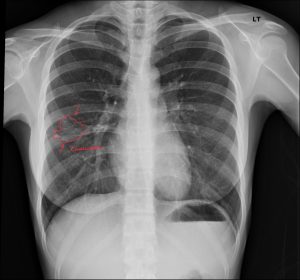

We are committed to enhancing patient care by delivering top-tier medical imaging evaluations and reports consistently. Our team of board-certified radiologists brings specialized expertise in diagnostic imaging, with a particular focus on chiropractic radiology that specializes in spine and musculoskeletal imaging. We strive to provide not just readings, but invaluable consultations, ensuring each patient receives the best that modern radiology has to offer. Our dedication to accuracy, speed, and reliability in off-site image interpretations sets us apart as trusted partners in healthcare.